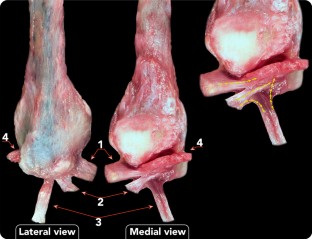

Connections were found in all cases between the ATFL and PTFL, the ATFL and CFL, and the CFL and PTFL. Connections between ATFL and PTFL were not homogeneous. Although connections between the ATFLif and PTFL were noted in all cases (40), only 17 ankles (42.5%) had connections between the ATFLsf and PTFL. The amount of fibres of connection was also variable.

Connections between the three components of the lateral collateral ligament of the ankle may be observed from the medial aspect of the ankle, and this may have important implications for arthroscopic lateral ligament repair.